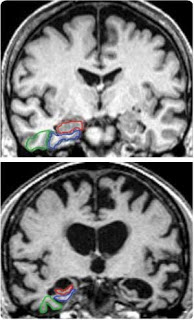

Pues esto, nada más y nada menos, es lo que han conseguido en el Instituto Ramón y Cajal del CSIC con una nueva tecnología microscópica que les permite reconstruir imágenes en tridimensoionales de las muestras cerebrales dañadas. Se han metido dentro de una placa de alzhéimer. Esto hace que a partir de ahora puedan ver miles de cosas nuevas que antes ni podían soñar.

Esta investigación aparecida en la revista Journal of Alzheimer?s Disease es muy importante para el conocimiento del alzheimer. Los investigadores ya tienen algunos datos reveladores, por ejemplo: las conexiones entre las neuronas, las sinapsis, llegan a ser hasta cinco veces más pequeñas en las zonas del cerebro que están afectadas por alzheimer.